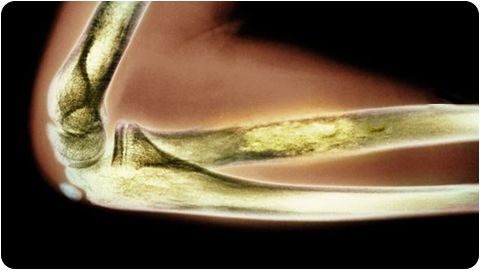

Ewing’s Sarcoma

Ewing’s sarcoma is a rare type of cancer that typically affects children and young adults, though it can occur at any age and mostly occurs in and around the bones.

Typically, this can occur in any bone, but mostly begins in the leg bones and hip bones, as well as the bones in the arms, chest, skull and spine. Ewing’s sarcoma hardly ever occurs in the soft tissues of the arms, legs, abdomen, chest, neck and head.